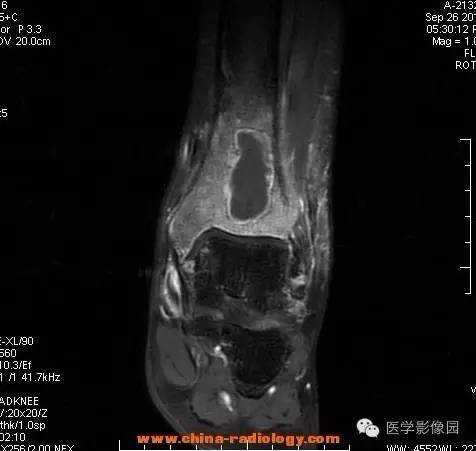

【病例】胫骨骨脓肿1例MR影像表现

影像学表现:胫骨中下段干骺端不未规则形长T1长T2信号,T2WI见不完整环形稍低信号影,T2脂肪抑制低信号更明显,并见胫骨下段及踝关节后外侧软组织呈弥漫稍高信号,增强明显不均匀强化,增强见低信号环内有环形强化影。

影像学表现:表现为长骨干骺端有椭圆形密度减低区,边缘有清晰的骨质硬化,病变与邻近正常骨髓腔境界清楚。MRI上T1WI呈低信号,少数呈等信号,T2WI多为混杂高信号,增强扫描可见环状强化,强化的脓肿壁薄而均匀。